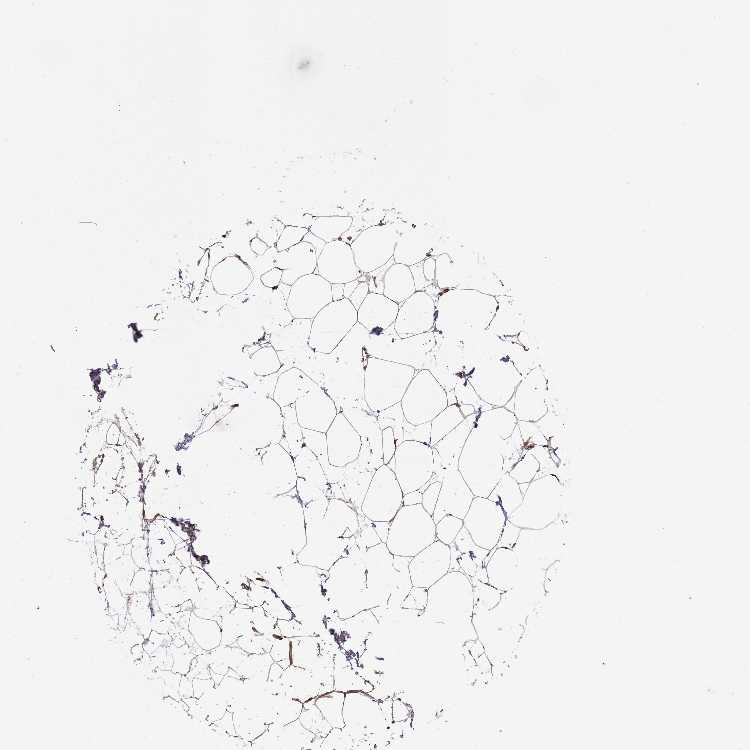

SOFT TISSUE 2 - Antibody stainingi

Antibody staining in the annotated cell types in the current human tissue is reported as not detected, low, medium, or high, based on conventional immunohistochemistry profiling in selected tissues. This score is based on the combination of the staining intensity and fraction of stained cells.

Each image is clickable and will lead to virtual microscopy that enables deeper exploration of all samples and also displays staining intensity scores, fraction scores and subcellular localization as well as patient and tissue information for each sample.

Antibody HPA047126Antibody HPA054655

Fibroblasts Not detectedNot detected

Peripheral nerve -High